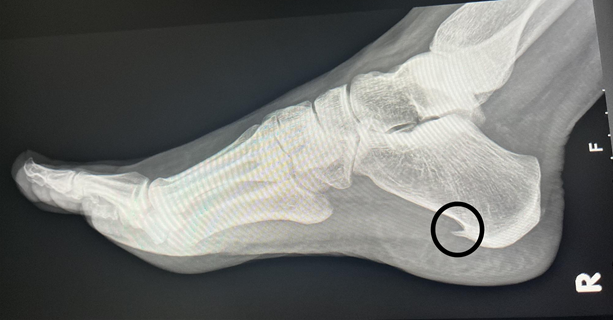

Iako se iza naziva petni trn krije mali koštani izdanak koji se formira na donjem dijelu pete, problem nije sam trn, već upala tkiva koja ga okružuje. Upravo ta upala izaziva bol, ukočenost i otežano kretanje.

Petni trn (lat. calcaneal spur) predstavlja naslagu kalcija koja se nakuplja na petnoj kosti, najčešće na mjestu gdje se vezuje plantarna fascija – čvrsta vezivna traka koja povezuje petu s prstima i podržava svod stopala.